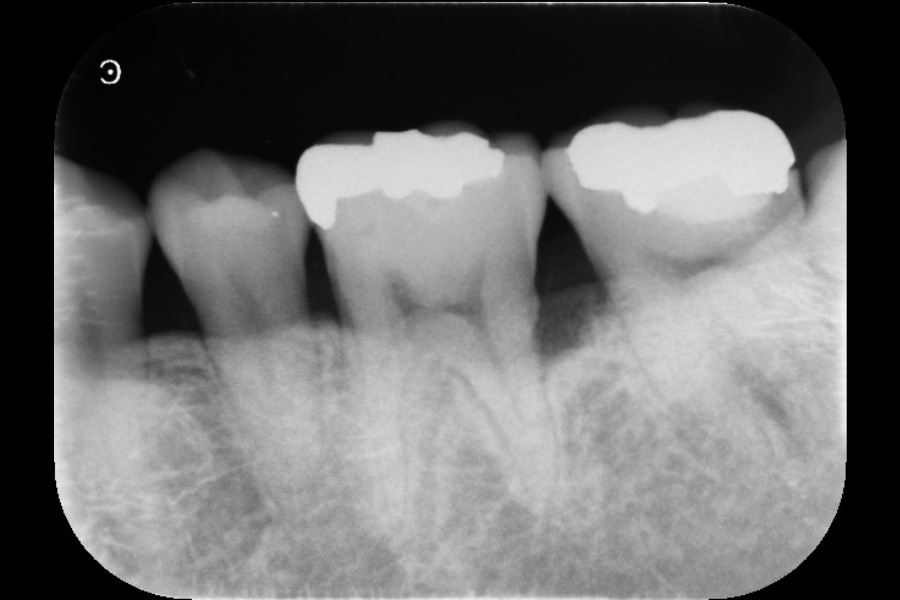

左上奥歯の歯ぐきが腫れて、噛むと痛い

【歯周組織再生療法】

- 主訴

- 左上奥歯の歯ぐきが腫れて、噛むと痛い

- 治療内容

- 左上4遠心と左上6近心に垂直性骨吸収が認められたためエムドゲインと骨補填材を用いて歯周組織再生療法を行った